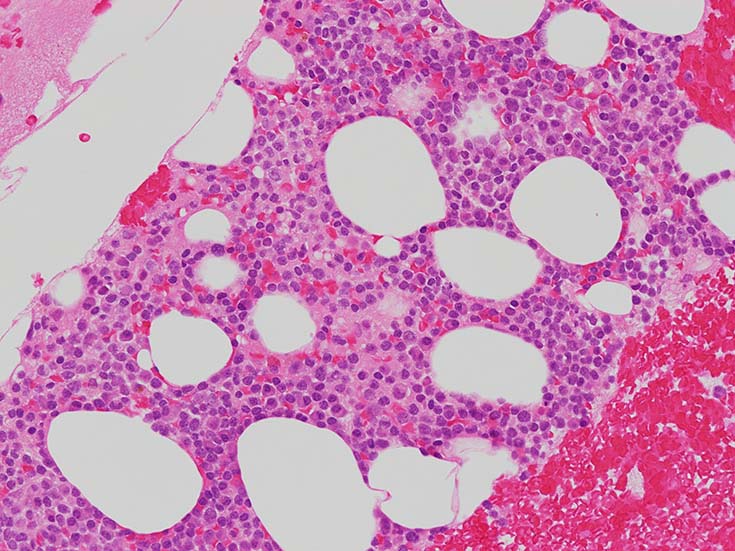

cellularityは60-70%. 赤芽球血島形成はみられない. Naphtol-ASD-CAE染色に赤染される顆粒球系細胞もごくわずか. 成熟Mgkもごく少数で, 正常造血は強く抑制されている.

類円形あるいは, シワのみられるconvolutedな核に核小体をもつN/C比大の細胞が増加している. クロマチンは微細で核は淡明にみえる.Naphtol-ASD-CAE染色陰性.幼若あるいは活性化されたリンパ球様細胞に似ている.

N/C比 70-90%, 中型芽球様細胞が増加. 核は類縁液核網繊細, 明瞭な核小体が 1-数個 細胞質は淡青色 MPO陰性.

中型芽球様細胞増加 N/C=70-90%, 核は類縁液核網繊細 明瞭な核小体が 1-数個 細胞質は淡青色 MPO陰性.